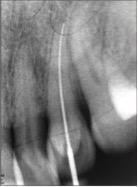

Το ακριβές μήκος του δοντιού, όπως και το μήκος εργασίας, το μετράει ο οδοντίατρος με ακτινογραφίες.

Αφού έχετε τελειώσει τη θεραπεία πρέπει να επισκέπτεστε κατά τακτά χρονικά διαστήματα, που ο οδοντίατρος θα σας ορίσει το ιατρείο για παρακολούθηση. Π.χ. σε περίπτωση ακρορριζικής βλάβης θα ελεγχθεί με ακτινογραφία η πορεία επούλωσης. Ενώ άλλες φορές μπορεί να κριθεί σκόπιμο να συμπληρωθεί η θεραπεία με ακρορριζεκτομή.